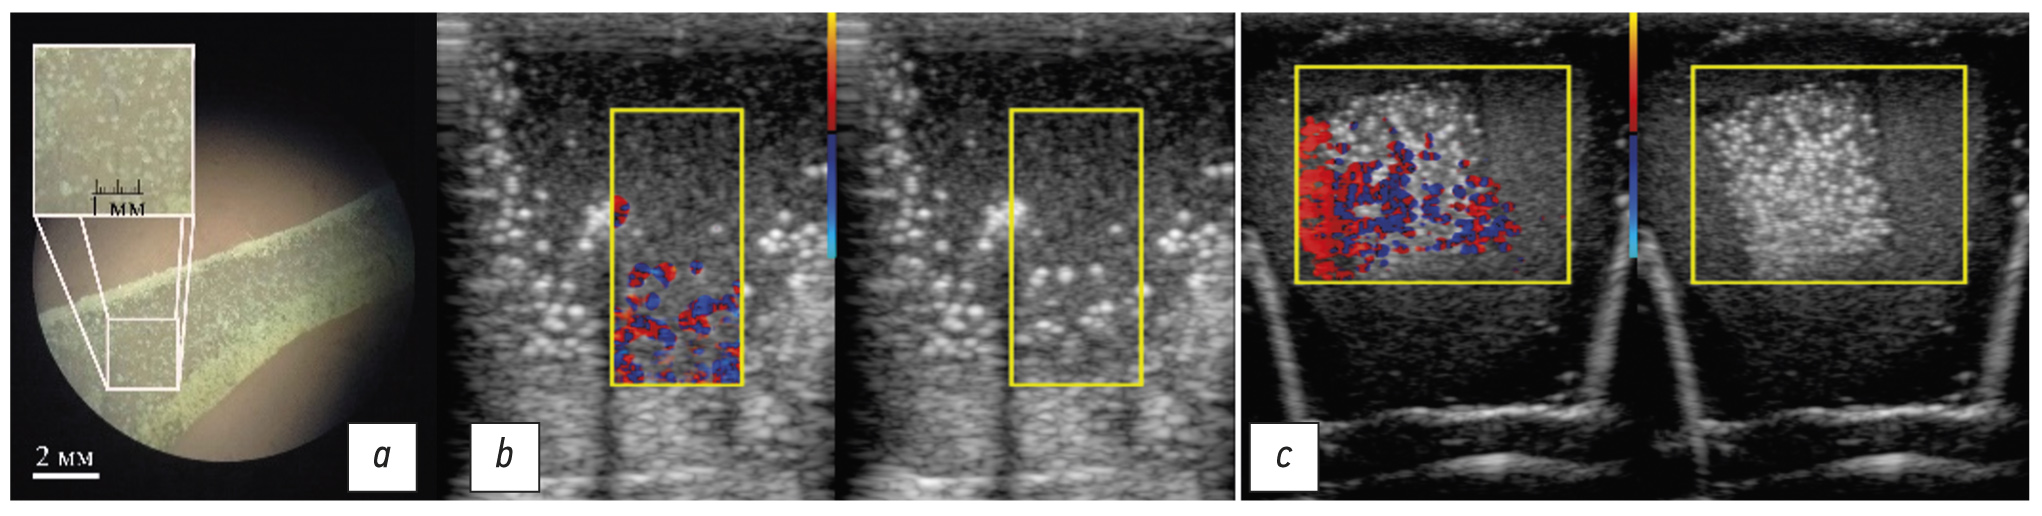

- A set of examinations of the custom phantom (Fig. 8; a detailed description of the phantom is available in [32]).

In the phantom study, the linear transducer was applied in fixed numbered positions. Cylinders, with a diameter of 1.75 mm, made of metal (positions 1, 4, and 8), plastic (positions 2, 5, and 7), and wooden rods (positions 3 and 6) in various media (water, alcohol, and agar-agar) were assessed. The set contains examinations that were conducted using a linear transducer at nine probing pulses and a pulse repetition rate of 1 kHz. Typical sonograms are shown in Fig. 9. If the phantom was filled with ethanol, the twinkling artifact was manifested much less frequently in contrast to other media used. In water, the artifact was also noticeable on the air bubbles that rose from the wooden rod. In addition, the twinkling intensity on aluminum rods was noticeably greater than that on plastic and wooden rods.

Fig. 9. Examples of sonograms of a specialized phantom with positions and a filling medium: a, position 2 (four plastic rods, which are located parallel to the sensor plane); b, position 3 (four wooden rods with their sides facing the sensor); c, position 4 (four aluminum rods with their sides facing the sensor); d, position 10 (wood, aluminum, and plastic rods with their sides facing the sensor).